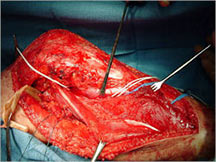

Surgery:

- Wide surgical resection/limb salvage

- Amputation for large unresectable tumors and other rare instances

Limb Sparing Surgery

- Surgical principles are the same as those employed for conventional osteosarcoma

- Nowadays, most patients can be treated with a limb sparing resection instead of an amputation

- Prosthetic replacements, cadaver allografts, vascularized bone grafts as well as other methods have been used to reconstruct extremities after tumors are removed